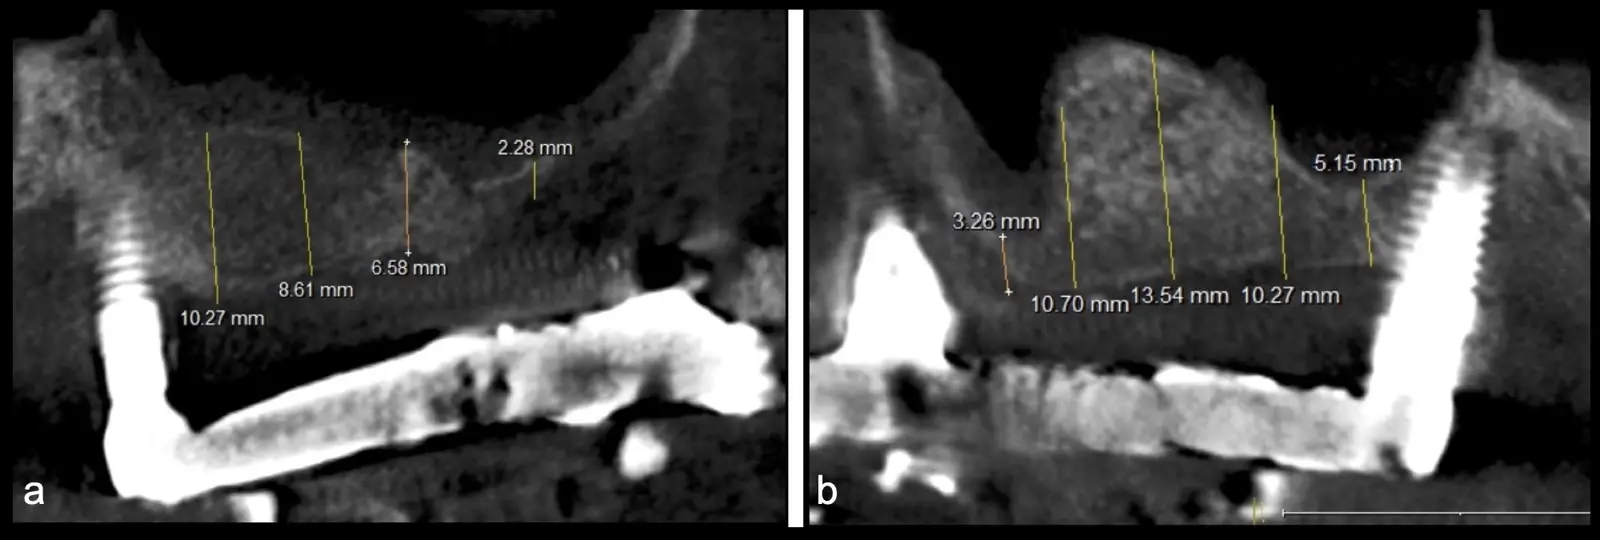

Paciente de 62 años, de sexo masculino, llega a la consulta para la colocación de implantes dentales. Refiere haber tenido tratamiento previo con implantes dentales, algunos de los cuales fueron perdidos. A la evaluación clínica se observa ausencia de piezas dentarias en el maxilar superior y 3 implantes remanentes. En la evaluación tomográfica se observa neumatización de los senos maxilares del lado derecho e izquierdo (Figura 14), para lo cual se indica el procedimiento quirúrgico de levantamiento de piso de seno maxilar en ambos cuadrantes, como paso previo a una nueva planificación implantosoportada.

Figura 14. Evaluación intraoral en donde se evidencia presencia de una prótesis híbrida soportada sobre implantes dentales, al retiro de la estructura se observó tornillo protésico fracturado (a, b, c). Evaluación tomográfica: corte sagital a nivel de los senos maxilares derecho e izquierdo, donde se observa una atrofia severa de los rebordes óseos acompañados de neumatización de los senos maxilar (d, f, g).

Figura 31. Control tomográfico post operatorio: corte sagital de ambos senos maxilares. (derecha e izquierda).